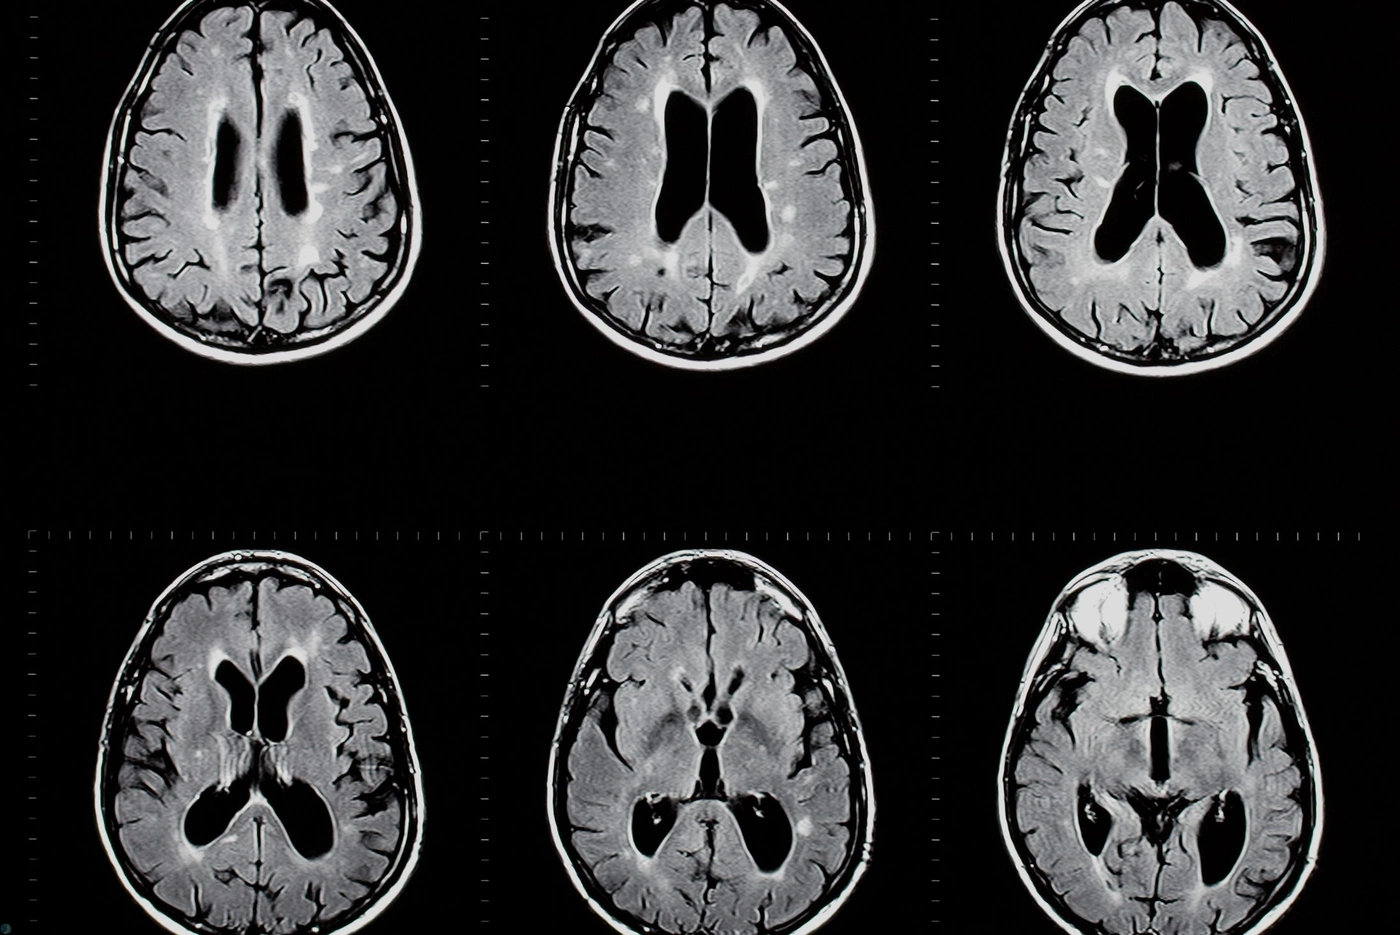

ام اس خاموش (Silent MS یا Radiologically Isolated Syndrome - RIS) وضعیتی است که ضایعات مغزی شبیه ام اس در MRI دیده می‌شود، اما علائم بالینی واضحی ندارد. علائم خفیف و اغلب نادیده گرفته‌شده شامل خستگی مزمن، مشکلات خفیف حافظه یا تمرکز، احساس گزگز یا بی‌حسی گذرا، ضعف عضلانی جزئی و اختلالات خلقی مانند افسردگی خفیف است. بسیاری افراد سال‌ها بدون علامت قابل توجه زندگی می‌کنند، اما حدود نیمی از موارد در ۵–۱۰ سال به ام اس علامت‌دار (CIS یا RRMS) پیشرفت می‌کنند. تشخیص با MRI تصادفی و پیگیری منظم انجام می‌شود. درمان زودرس (مانند ویتامین D یا داروهای پیشگیری) می‌تواند پیشرفت را کند کند.

مولتیپل اسکلروزیس یا ام‌اس یکی از پیچیده‌ترین بیماری‌های عصبی است که می‌تواند ماه‌ها یا حتی سال‌ها بدون علامت مشخص باقی بماند. در بسیاری از افراد، نشانه‌های اولیه آن آن‌قدر خفیف، مبهم یا گذرا هستند که به‌سادگی با خستگی، استرس، کمبود خواب یا مشکلات روزمره اشتباه گرفته می‌شوند. به همین دلیل، شکل پنهان یا خاموش این بیماری اغلب دیر تشخیص داده می‌شود؛ در حالی که تشخیص زودهنگام می‌تواند نقش مهمی در کنترل پیشرفت بیماری و بهبود کیفیت زندگی فرد داشته باشد. به دلیل اهمیت تشخیص به موقع این بیماری ما در ادامه این مقاله درباره علائم ام اس خاموش به طور مفصلی صحبت خواهیم کرد.